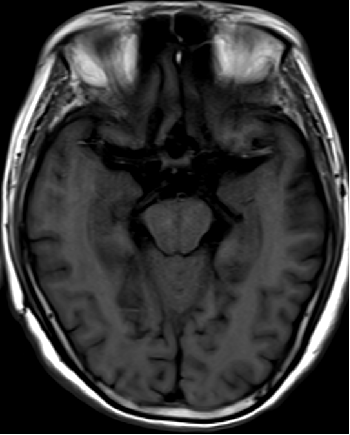

2013-8-2 CT

腰穿脑压240